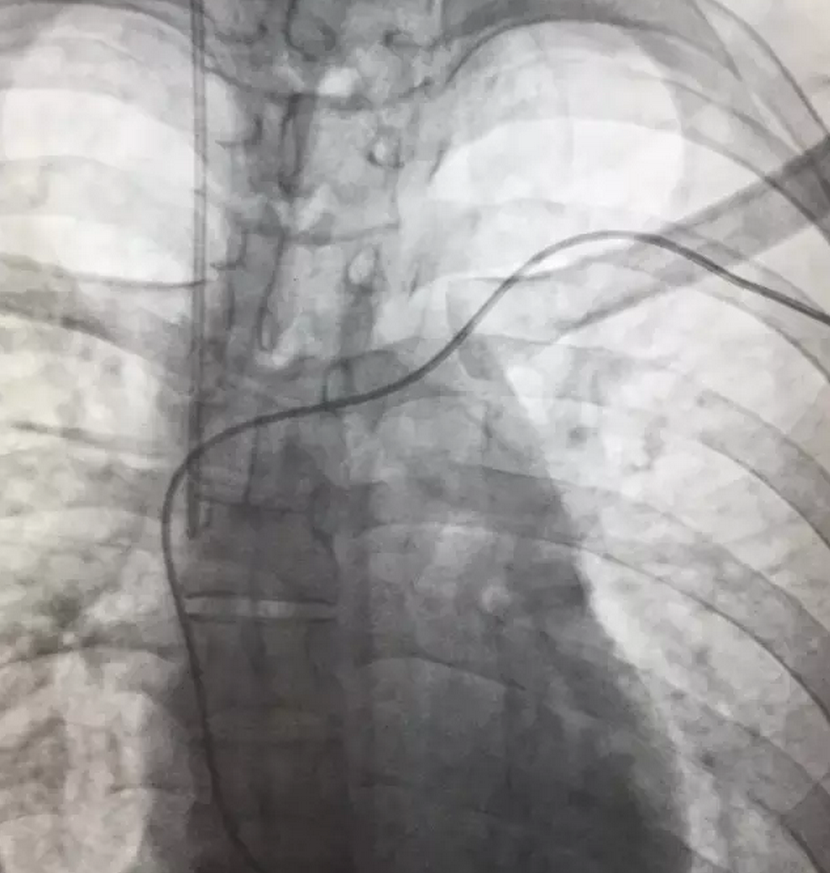

入院后,心內(nèi)科的值班醫(yī)生考慮,患者在院前曾出現(xiàn)抽搐、心跳停搏現(xiàn)象,心肌炎較為嚴(yán)重,心臟隨時(shí)有再次發(fā)生停搏的可能,于是馬上通知上級(jí)醫(yī)生進(jìn)行緊急會(huì)診,專家會(huì)診后決定,立即為病人緊急手術(shù)安裝心臟保護(hù)裝置-臨時(shí)起搏器。

手術(shù)過程有驚無險(xiǎn),手術(shù)在介入科DSA引導(dǎo)下進(jìn)行,在臨時(shí)起搏導(dǎo)管送入到右心室時(shí),病人突然出現(xiàn)神志不清、四肢抽搐,心電監(jiān)護(hù)顯示患者再次出現(xiàn)心室停搏,手術(shù)醫(yī)生們臨危不亂,果斷為病人實(shí)施各項(xiàng)搶救措施的同時(shí)立即連接并啟動(dòng)起搏器。病人心跳馬上恢復(fù),隨后轉(zhuǎn)醒。經(jīng)過差不多一個(gè)小時(shí),患者順利安裝了臨時(shí)心臟起搏器,并轉(zhuǎn)入心內(nèi)科重癥監(jiān)護(hù)病區(qū)密切觀察和治療。